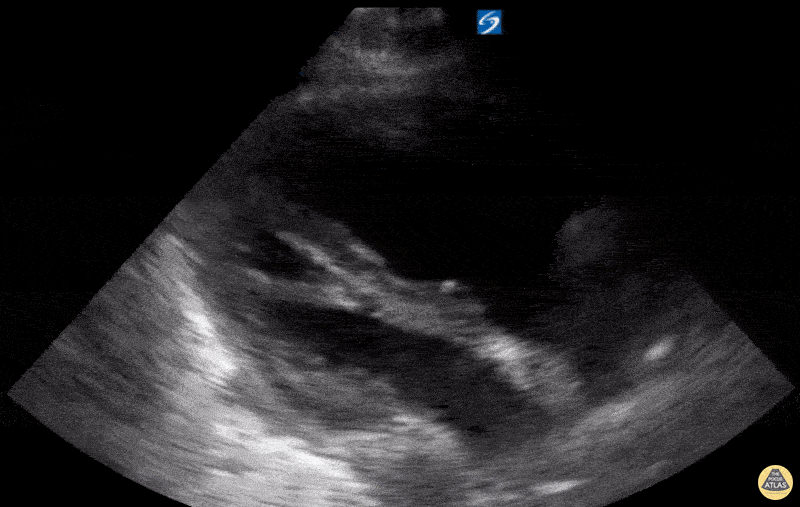

Right Ventricular Dysfunction - RV Strain with RV dilation on PSLA

A 70-year-old patient with Chronic Obstructive Pulmonary Disease (COPD) (not on home oxygen) presented to the ED with acute worsening dyspnea with persistent hypoxia despite supplemental oxygen, tachypnea, and increased work of breathing. There was no infectious or environmental exposure to explain the patient’s presentation. The patient’s differential diagnosis included acute pulmonary embolism (PE) and COPD exacerbation/progression. Parasternal long-axis (PSLA) and short-axis (PSSA) views showed RV dilatation with RV strain. The RV strain was demonstrated by flattening of the interventricular septum,. Also, it shows hyperdynamic LV from tachycardia with near obliteration of the LV cavity in systole. CT angiography scan showed no evidence of PE. The patient was admitted and diagnosed with a progression of severe COPD with pulmonary hypertension and right ventricular remodeling. Contributed by: Hassan Alshaqaq, MBBS, Emergency Medicine Resident at King Saud University Medical City, @HassanAlshaqaq